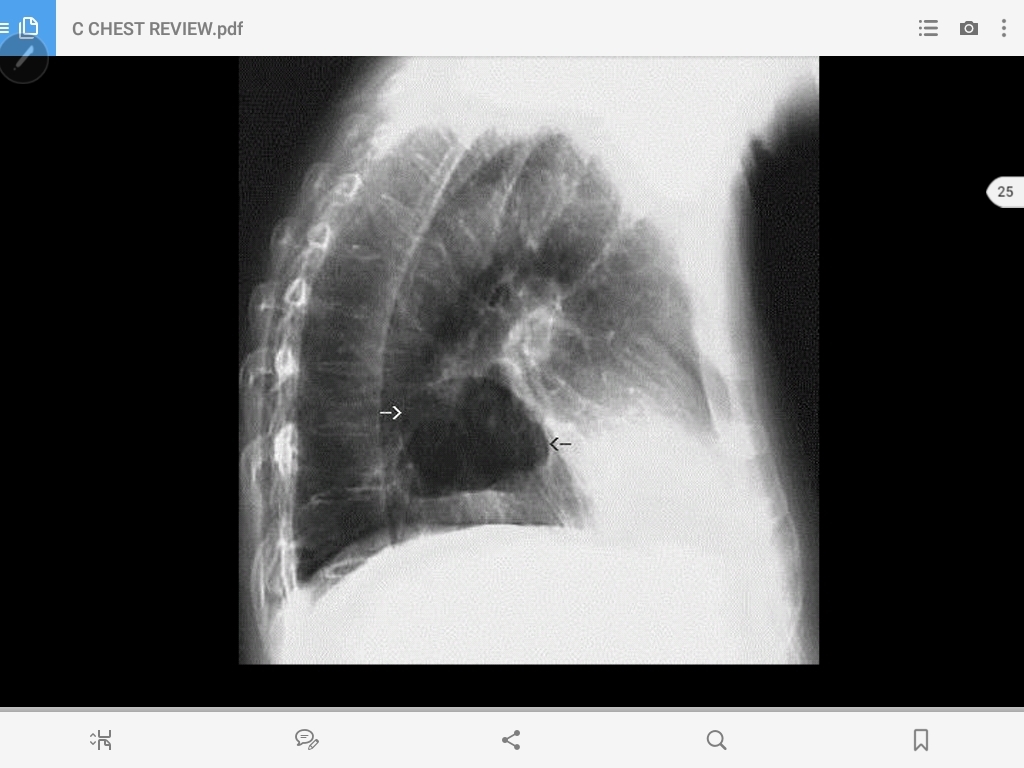

pneumothorax